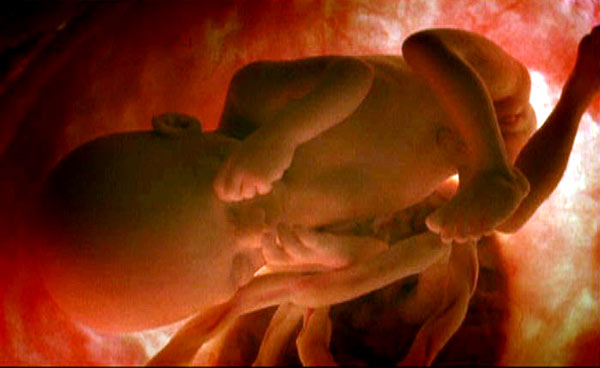

Primeras sensaciones. El feto tiene entre 6 y 7 meses. Ya percibe sensaciones a través del gusto y el oido. Abre los ojos y hace movimientos.

Primeras sensaciones. El feto tiene entre 6 y 7 meses. Ya percibe sensaciones a través del gusto y el oido. Abre los ojos y hace movimientos.